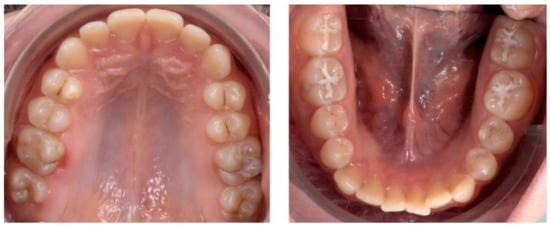

3. Results